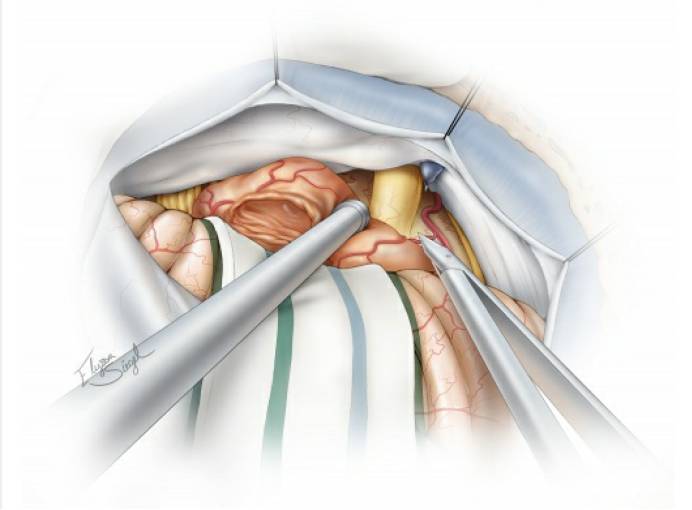

图8. 下一步,使用超声吸引器对肿瘤进行瘤内减压。血供已断的肿瘤减压效率更高,因为此时不需要在瘤腔内重复“切除-止血”的步骤。注意,肿瘤前面的包膜需完整保留,勿大意损伤。

图9. 充分的瘤内减压使得肿瘤包膜移动灵活,从而无需对正常组织结构进行不必要的牵拉。然后将肿瘤下极包膜与后组颅神经进行锐性分离。注意仔细保留包绕神经的蛛网膜,细致松解粘连的血管。